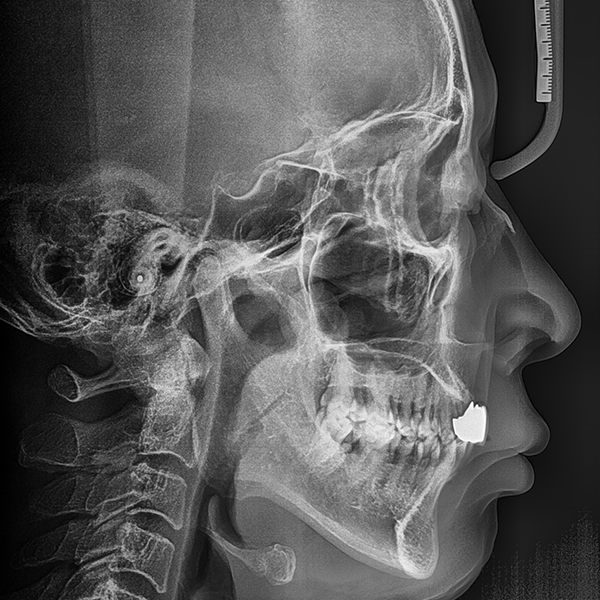

3. Тохиолдол.110 60-аад насны И*Гэ 2020-01-20 / 2020-3-21

Нэг өдрийн шүдний эмнэлэг

상악/앞니 부분 / 3개이하 / 뼈이식|고혈압

Тохиолдол.110 60-аад насны И*Гэ 2020-01-20 / 2020-3-21

Before Before

After After